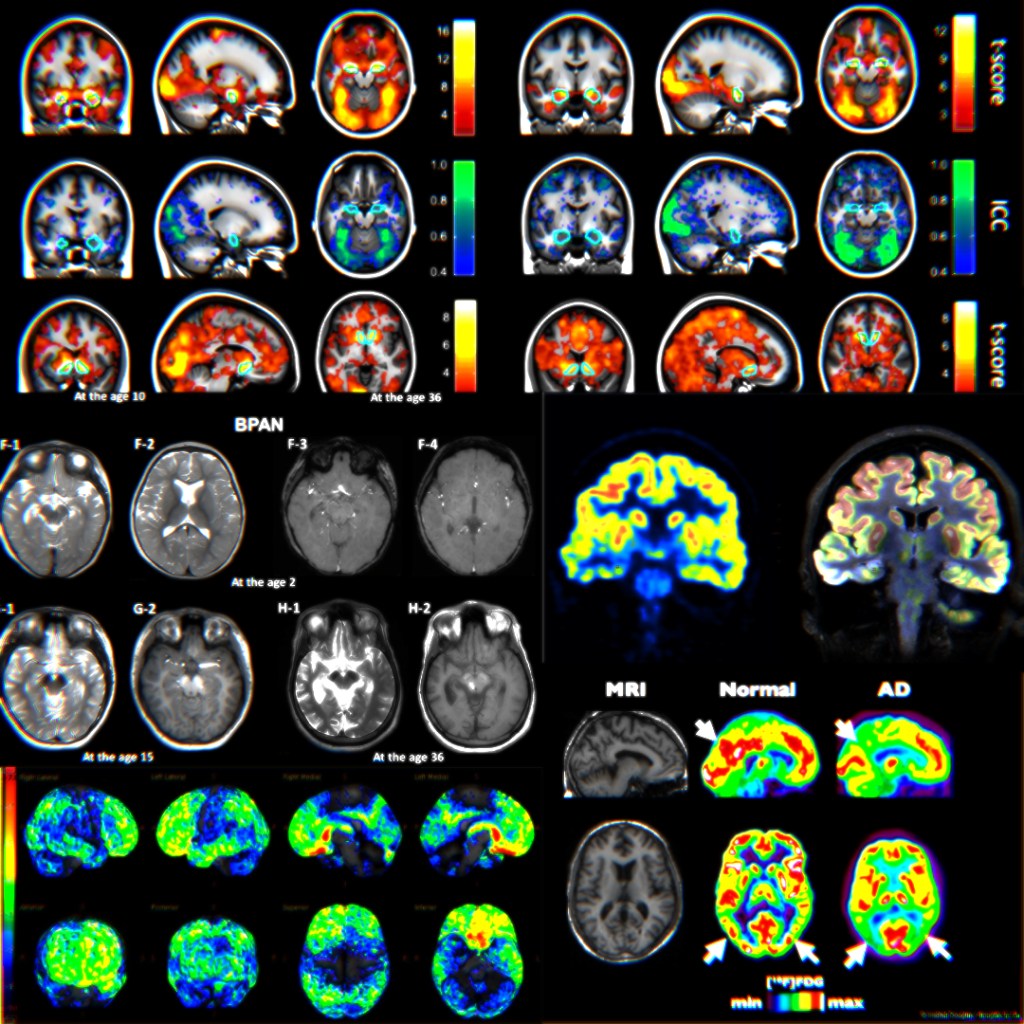

Here are some fMRI brain scans.

They could show the brain when shown a video of bullying. See how the colourful blobs light up? Red here, blue there, yellow scattered around here and there. The caption could say “Bullying causes an acute alarm state in the brain”.

It looks scientific. It looks important. But what does it actually tell you?

That brains do stuff when you see a video. Which, okay. Where else would the thinking happen? Your elbow?